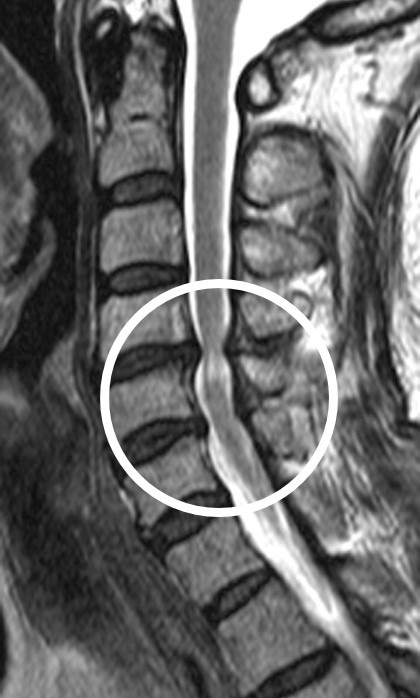

경추척수증은 경추(목뼈) 부위의 신경이 압박을 받아 손상되는 질환으로, 손 움직임이 어렵거나 걷기 힘들어지는 등 운동신경·감각신경 마비를 유발할 수 있다. 치료법은 척수신경이 지나는 부위(후궁)를 열고 압박을 풀어주는 ‘경추후궁성형술’이다. 수술 후 모든 환자는 예후를 추적 관찰하기 위해 수술 후 1년 동안은 수개월에 한 번씩, 2년부터는 매년 한 번씩 정기적으로 외래진료를 받아야 한다.